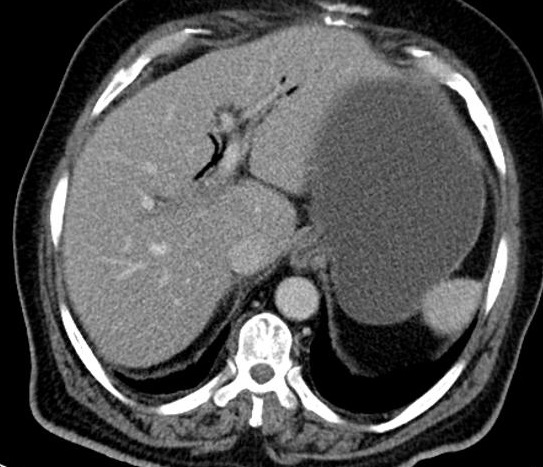

Image TDM :

Image radiologiquer TDM de syndrome de Mirizzi est la

presence de calcul et une epaisissement de la paroi vesicule

biliaire rehaussement hyperdense par le contrast . La dilatation de voie

biliaire pricipale ( canal hepatique commune ) peut se

en voyait . .

Image une calcul a

infundubulum du vesicule biliaire ( fleche

rouge ) avec epaississement de la paroi

vesiculaire : Image TDM en coupe axiale

avec contrast intraveineuse |

Meme cas en coupe coronal ( frontal ) :

Image de calcul hyperdense se en voyait tres net (

fleche rouge ) avec image de vesicule biliaire

inflamee et la dilatation de canal hepatique commun |